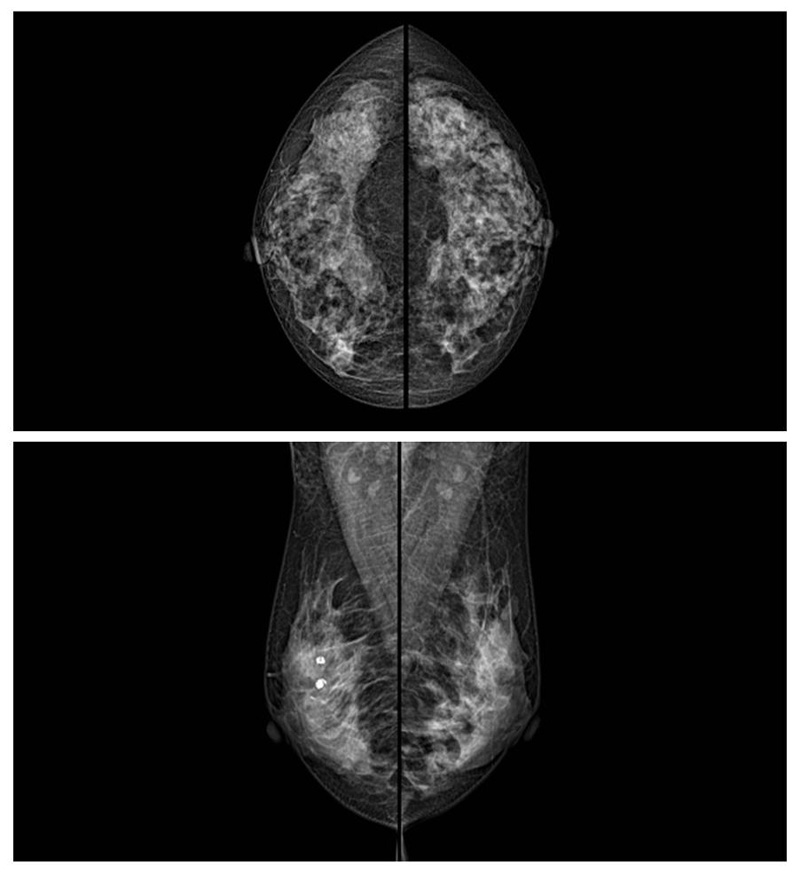

乳腺癌的發(fā)生率越來(lái)越高,已經(jīng)是我們國(guó)家的癌癥之一已成為女性健康“頭號(hào)殺手”。乳腺DR可提高乳腺癌早期檢出率并精準(zhǔn)定位。發(fā)現(xiàn)和診斷早期乳腺癌最有效的方法之一,明顯利大于弊女性都要重視乳腺的檢查。輻射很小最簡(jiǎn)便、最可靠、無(wú)創(chuàng)性檢查手段,做一次乳腺DR的劑量相當(dāng)于7周的正常生活。尤其是對(duì)于40歲以上的女性尤為重要,那么乳腺DR是怎么進(jìn)行檢查的呢?我們來(lái)了解一下,為廣大朋友在檢查前有點(diǎn)心理準(zhǔn)備。檢查時(shí)候是避開(kāi)經(jīng)期的前后,月經(jīng)來(lái)后的7天左右比較合適。需要脫衣服檢查,根據(jù)拍片的擺位要求,有頭尾位置,內(nèi)外斜位,還有側(cè)位。定點(diǎn)放大壓迫方法可以更細(xì)微清晰的檢查出病灶。